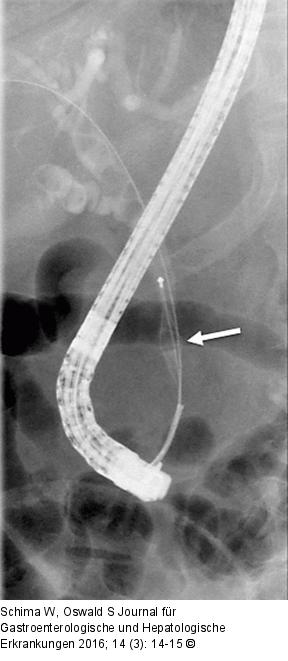

Abbildung 3B: Choledochuskonkrement Nach mechanischer Lithotripsie mittels Dormiakörbchen konnten die Konkrementreste endoskopisch geborgen werden. |

Nach mechanischer Lithotripsie mittels Dormiakörbchen konnten die Konkrementreste endoskopisch geborgen werden. |